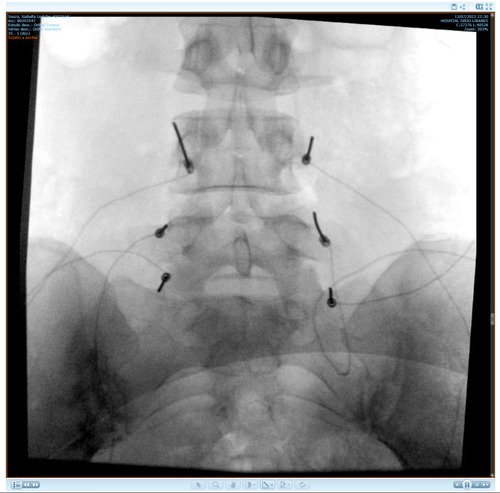

Não sei por onde começar porque e uma história longa e vou tentar resumir, fiquei meses tentando descobrir que eu tinha fibromialgia, porém eu não tenho só isso, tive edemas na coluna, problemas na lombar, e até derrame pleural eu tive, eu pago aluguel que e 1300 mais o condominio que e 450, fora que eu me planejei e não tenho familia pra apoiar entre outras coisas, quando me mudei e planejei pra poder ter o proprio ape eu não sabia que do nada iria ficar doente, em março de 2023 eu pego as chaves mas até la ta dificil, fiz emprestimo e várias outras coisas porque só a medicação de durogesic que eu uso e restiva um a caixa e 650 e o outro 300, podem pesquisar, após um procedimento na lombar cirurgico pra tentar aliviar a dor descobri uma necrose asseptica na cabeça dos dois femur, com risco de ter que colocar uma protese, até pouco tempo estava de muleta, só podia ficar sentada, e mesmo a dor e muito forte, eu ainda não sei a tal outra doença que eu tenho, já aconteceu de eu entrar na emergência e ficar na UTI, tive mais de 10 internações no hospital e não e mentira, minha maior luta e conseguir tratar essa necrose, poder voltar a praticar esportes, sei que tem gente que precisa muito mais mas eu cheguei no meu limite e to até com um aluguel atrasado, todas as coisas que eu estiver pagando eu vou colocar nota fiscal porque eu não to aqui pra fazer ninguém de trouxa, vou colocar exame, fotos de internação entre outras coisas que posso, porque tem algumas que não posso devido porque não quero imagem negativa para local de trabalho (e aonde eu trabalho eles estão me ajudando e muito), e de acordo de como for funcionando a vakinha eu vou vendo se aumento, eu só queria me livrar dessas contas sufocantes primeiro, e agora os médicos estão lutando pra descobrir a outra doença que tenho além dessa da necrose que ta me deixando muito mal e que a fibromialgia atrapalha a descobrir, sei que e chato porque já pedi ajuda 2 vezes, mas conversei com amigos e infelizmente eu não tenho outra opção a não ser pedir ajuda, vou colocar exame de tudo etc, o valor até de emprestimos que estou devendo e tudo mais, e podem me perguntar qualquer coisa que eu respondo e claro, vou postar nota fiscal pra provar que to pagando o que to mostrando, eu to no meu limite, e não e fácil, eu ficava 3 dias seguidos sem conseguir dormir e os médicos não conseguiam descobrir e ainda sigo firme no tratamento porque vou encontrar uma resposta e não posso desistir do tratamento, eu poderia fazer um textao aqui mas com poucas palavras já consigo ser direta, obrigada a quem ajuda e continua me apoiando desde o começo e pra quem não gosta e não acredita e só não ajudar, ninguém vai ficar inventando internações etc pra ficar ai pedindo dinheiro de graça pra ostentar, não gosta só não infernizar, só cada um sabe o sofrimento que ta passando na própria pele e a sua luta diária, agradeço se puder ajudar, aceito tudo que seja positivo e desejo o dobro de bom pra cada um.